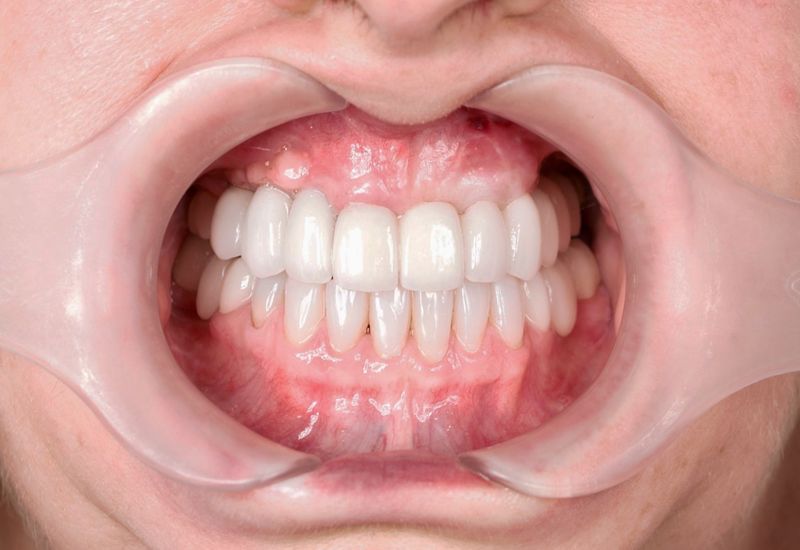

Samodzielna korona nie obciążająca zębów sąsiednich - to dzisiaj możliwe.

+ brak konieczności szlifowania zębów

+ brak zalegania resztek pokarmowych pod mostem

Wszczepienie implantu na ogół jest zabiegiem bezbolesnym i nie wymagającym dłuższej rekonwalescencji.